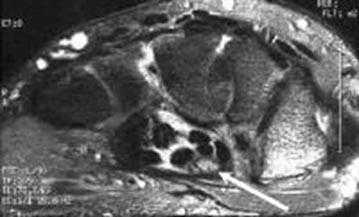

МРТ локтевого сустава в корональной плоскости. В подкожно-жировой клетчатке локтевого сустава отмечаются множественные образования неправильной вытянутой формы, местами сливающиеся между собой — вероятно, венозная мальформация.

МРТ локтевого сустава в сагиттальной плоскости. Отмечается повышенное скопление свободной синовиальной жидкости в полости локтевого сустава. Синовиальная оболочка умеренно гипертрофирована.

а) МРТ локтевого сустава в аксиальной плоскости

б)МРТ локтевого сустава в корональной плоскости. Общее сухожилие разгибателей в месте прикрепления к латеральному надмыщелку плечевой кости неравномерно утолщено, МР-сигнал от него неоднородно повышен на PD FS-ВИ и Т2-ВИ за счет выраженного отека и разволокнения (признаки латерального эпикондилита), общая целость его не нарушена. Окружающие мягкие ткани с признаками отека.